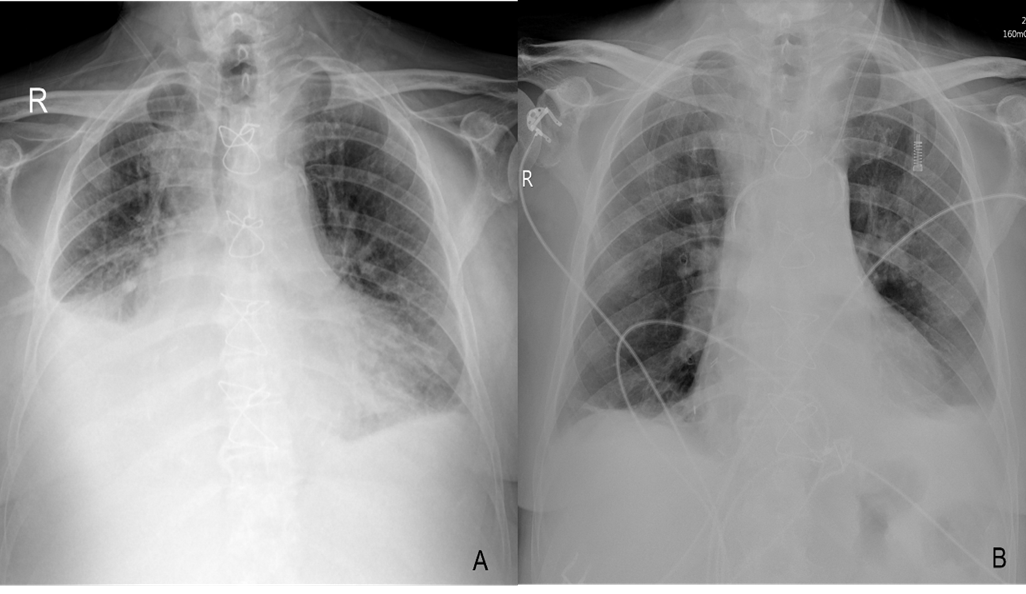

An Unusual Coronary Artery Complication after Surgery for a Complex Congenital Heart Disease: A Case Report

Zaher Faisal Zaher, MD